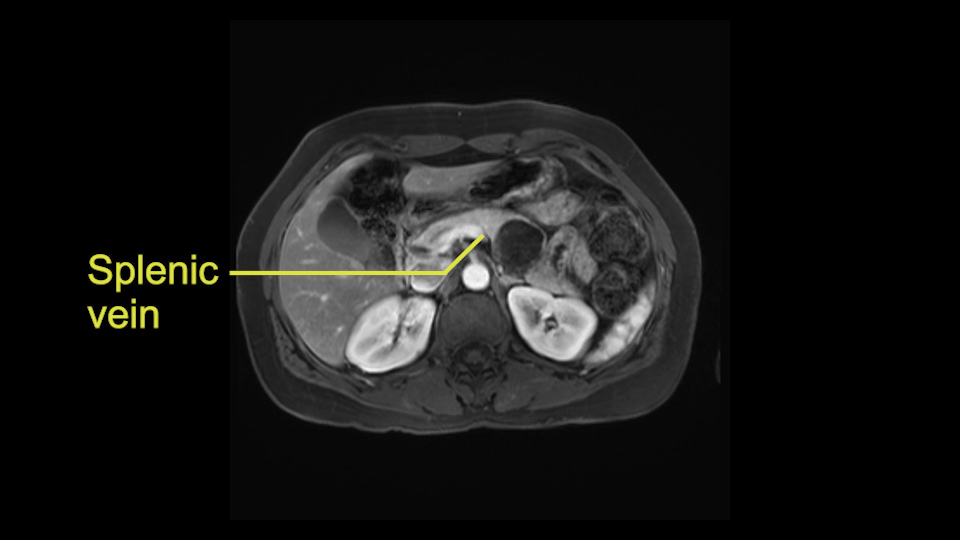

Other slowing down moments with this procedure include dissection of the splenic vein and splenic artery. These are technically challenging moments and important moments where care needs to be taken. Not only to avoid bleeding and injury to the vessels but also to ensure an adequate margin.

The lesion itself is quite adjacent to and abuts the splenic vein and therefore we need to anticipate that these two structures will be intimately related and possibly impossible to separate between the two.

The second slowing down moment or consideration I give to a distal pancreatectomy is the anatomy of the portal vein and the splenic artery. And so I look here and the anatomy is pretty straightforward. The splenic vein comes off normally and runs behind the pancreas and I can see the artery superior to that, again coming off in a normal manner from the celiac axis. So those two things, the portal vein and the splenic artery will be taken normally in this procedure.

So first step that we do: mobilize the splenic flexure first to visualize Gerota’s fascia and that would help bring down the colon and expose the pancreatic tail. So now that the pancreas is visible, division of the gastrocolic ligament will come into view. And a window can be created at the inferior edge of the pancreas to slowly lift the inferior edge to expose the splenic vein behind. This is the slow-down moment that I am talking about because the MR shows that there could be contact with the cyst. It’s important to know that to avoid perforation, to avoid rupture of the cyst, because we need to avoid touching the cyst, it is quite a size of 4.3 about 4cm.

I think the splenic vein, once I have slowly teased it off from the cyst and from the retropancreatic parenchyma, I would put a vessel loop around it to serve as a traction. So once you have the vessel loop or probably umbilical tape, to retract or pull the pancreatic parenchyma while we slowly tease it off and try to move superiorly to be able to expose the splenic artery. That is again another slow-down moment because sometimes we think that it is the splenic artery at the superior edge of the pancreas, but it could also be the hepatic artery as it branches from the celiac artery.